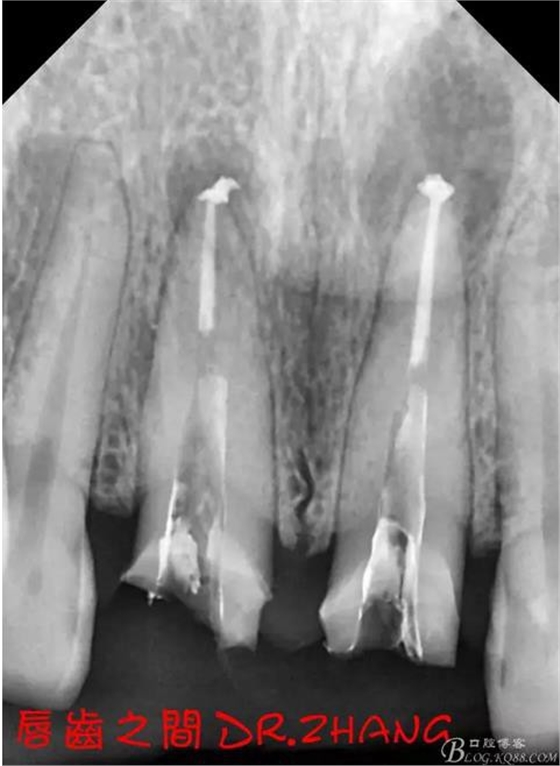

X片示11 21根管內(nèi)有高密度陰影 根尖低密度陰影

診斷:11 21慢性根尖炎

處理:21從修復(fù)體舌側(cè)打開通路 髓腔內(nèi)疑似纖維樁 高速和低速手機聯(lián)合去除樁核 在處理的過程中不斷拍片確認(rèn)方向 去除樁核后拔髓針去除牙膠 只有一個標(biāo)尖 膿液大量滲出 雙氧水和鹽水交替沖洗后 滲出減少 開放髓腔 隔日復(fù)診